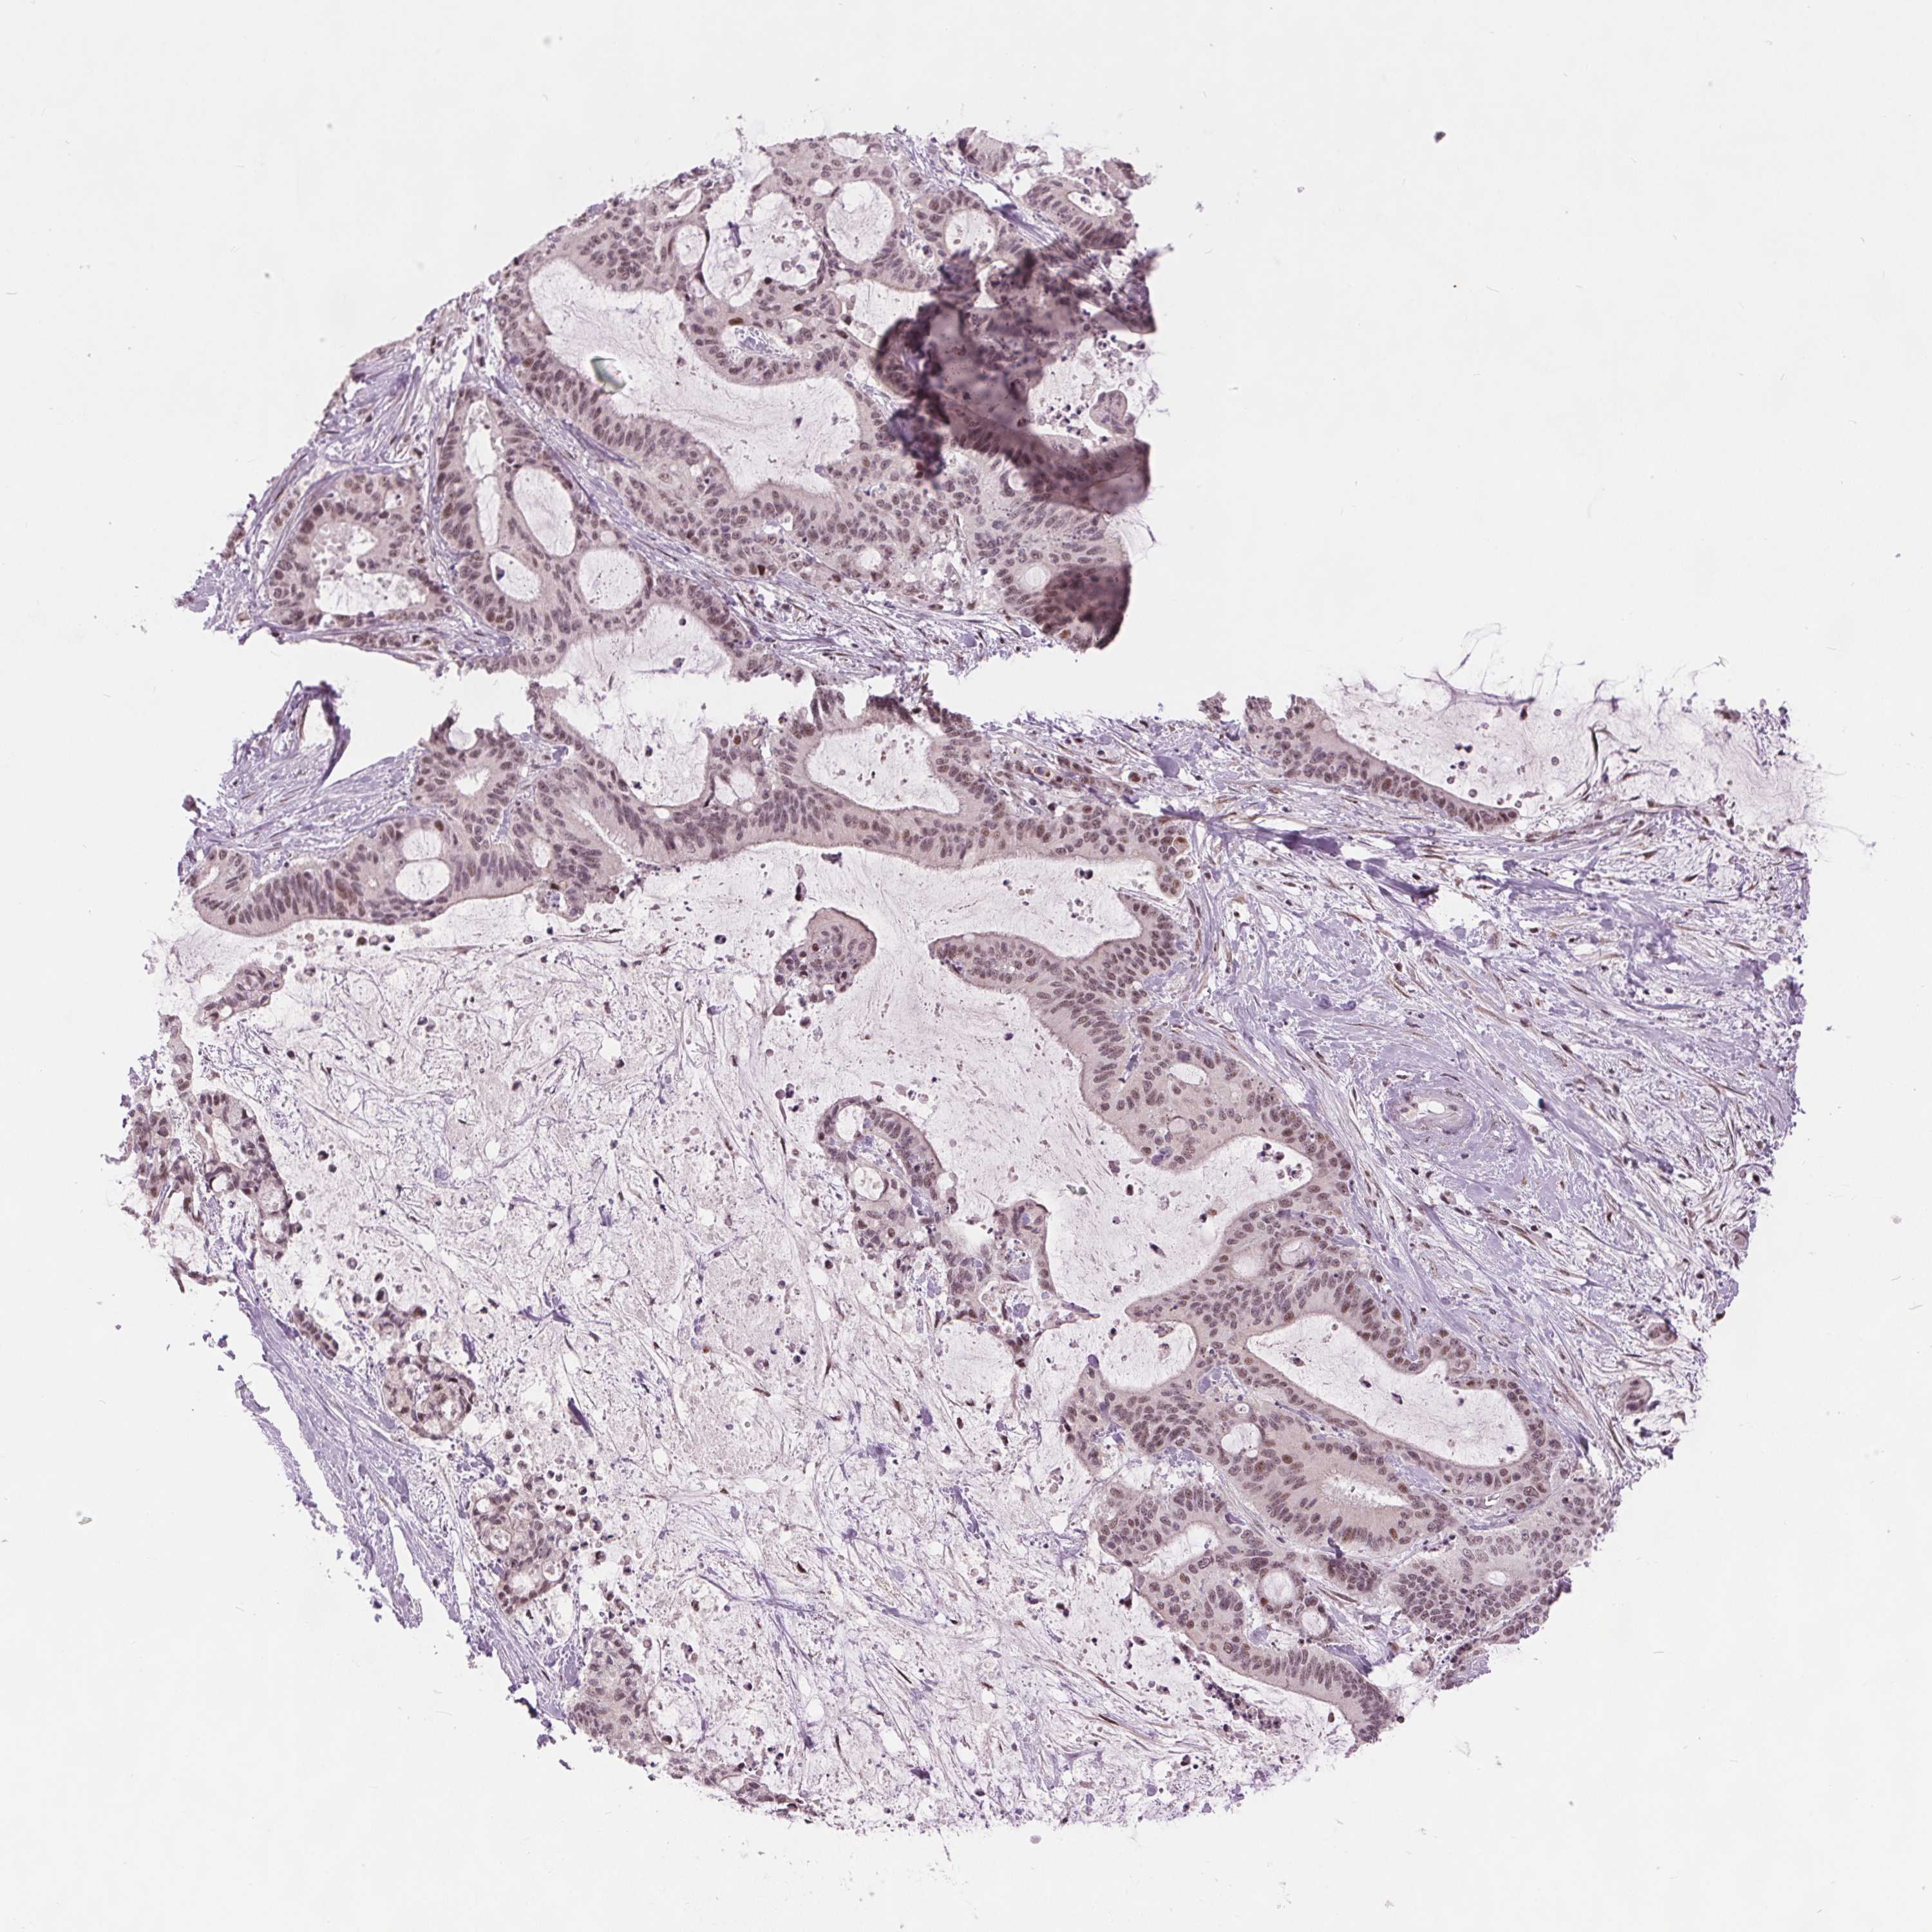

LIVER CANCER - Protein expressioni

A mouse-over function shows sample information and annotation data. Click on an image to view it in a full screen mode. Samples can be filtered based on level of antibody staining by selecting one or several of the following categories: high, medium, low and not detected. The assay and annotation is described here.

Note that samples used for immunohistochemistry by the Human Protein Atlas do not correspond to samples in the TCGA dataset.

Antibody stainingi

Antibody staining in the annotated cell types in the current human tissue is reported as not detected, low, medium, or high, based on conventional immunohistochemistry profiling in selected tissues. This score is based on the combination of the staining intensity and fraction of stained cells.

Each image is clickable and will lead to virtual microscopy that enables deeper exploration of all samples and also displays staining intensity scores, fraction scores and subcellular localization as well as patient and tissue information for each sample.

Antibody HPA066832

Staining

High

Medium

Low

Not detected

Intensity

Strong

Moderate

Weak

Negative

Quantity

>75%

75%-25%

<25%

None

Location

Nuclear

Cytoplasmic/membranous

Cytoplasmic/membranous,nuclear

Cholangiocarcinoma